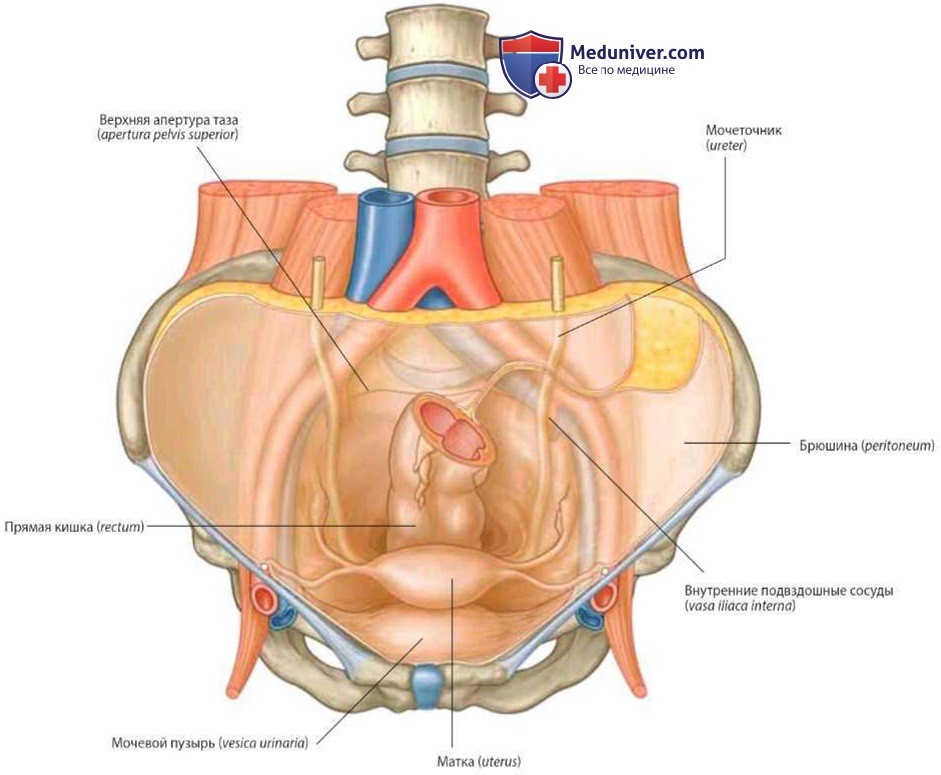

Анатомия малого таза: детальные схемы и изображения